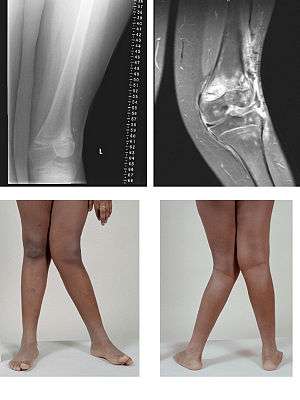

| Valgus Deformity MRI and photograph | |

In orthopedics, a valgus deformity is a condition in which a bone or joint is twisted outward from the center of the body.[1] The opposite deformation, where the twist is toward the center of the body, is called varus. Common causes of valgus knee in adults include arthritis of the knee and trauma.

Rheumatoid knee commonly presents as valgus knee. Osteoarthritis knee may also sometimes present with valgus deformity though varus deformity is common. Total knee arthroplasty (TKA) to correct valgus deformity is surgically difficult and requires specialized implants called constrained condylar knees.

- Knee: genu valgum (from Latin genu = knee) — the tibia is turned outward in relation to the femur, resulting in a knock-kneed appearance.